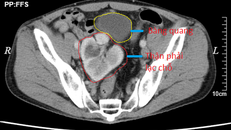

Hình ảnh chụp CT cho thấy thận phải lạc chỗ

(Ngày Nay) - Quả thận phải của nam bệnh nhân 61 tuổi nằm lạc chỗ xuống vị trí tiểu khung, được bác sĩ tìm cố định về đúng vị trí.